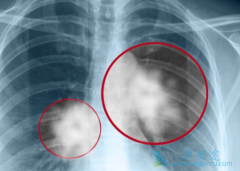

众所周知,肿瘤是严重危害人类生命健康的疾病。2018年肿瘤调查显示,目前我国每年新发肿瘤病人数在800万人左右,每分钟大概有4个人死于恶性肿瘤。在恶性肿瘤中,肺癌的发病率和死亡率都居首位。中国的肺癌死亡率和发病率仍旧居高不下,这也就对临床医生 ...